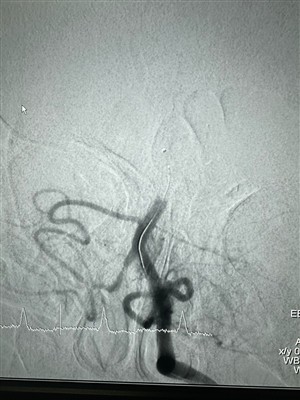

Συναρπαστική υπόθεση στο SRH Waldklinikum Gera στις 11 Απριλίου 2024!Μια ενδιαφέρουσα υπόθεση διεξήχθη πρόσφατα στο SRH Waldklinikum Gera, με επικεφαλής τον Dr. med. Kroeßner. Αυτή η περίπτωση αφορούσε τη χρήση ενός καθετήρα αναρρόφησης Glutton (6F) μαζί με ένα Dred...

Μια νέα περίπτωση με καθετήρα αναρρόφησης λαιμαργίαςΕίναι ενθουσιασμένος που μοιράζομαι μια επιτυχημένη υπόθεση από την Ολλανδία. Πληροφορίες Ασθενούς: Μεγαλύτερη κυρία με εγκεφαλικό m2. Χρήση προϊόντος: Καθετήρας αναρρόφησης Glutton. Χωρίς τίποτα α...

Μια νέα θήκη για το Dredger Stent RetrieverΠρόσφατα, υπήρξε μια επιτυχημένη περίπτωση θρομβεκτομής χρησιμοποιώντας το Dredger Stent Retriever της NeuroSafe Medical Co., Ltd. Το Dredger Stent Retriever έχει ένα μη επεμβατικό μαλακό άκρο, το ...

Νέα υπόθεση χρησιμοποιεί ένα Dredger Stent RetrieverΈνας 48-άρρενος ασθενής ετών με οξεία δεξιά ημικάρεση στο παράθυρο θρομβεκτομής (4 ώρες). Πριν και μετά τη θρομβεκτομή με χρήση stent retriever Dredger (30x30) στην πορεία του rami terminalis super...